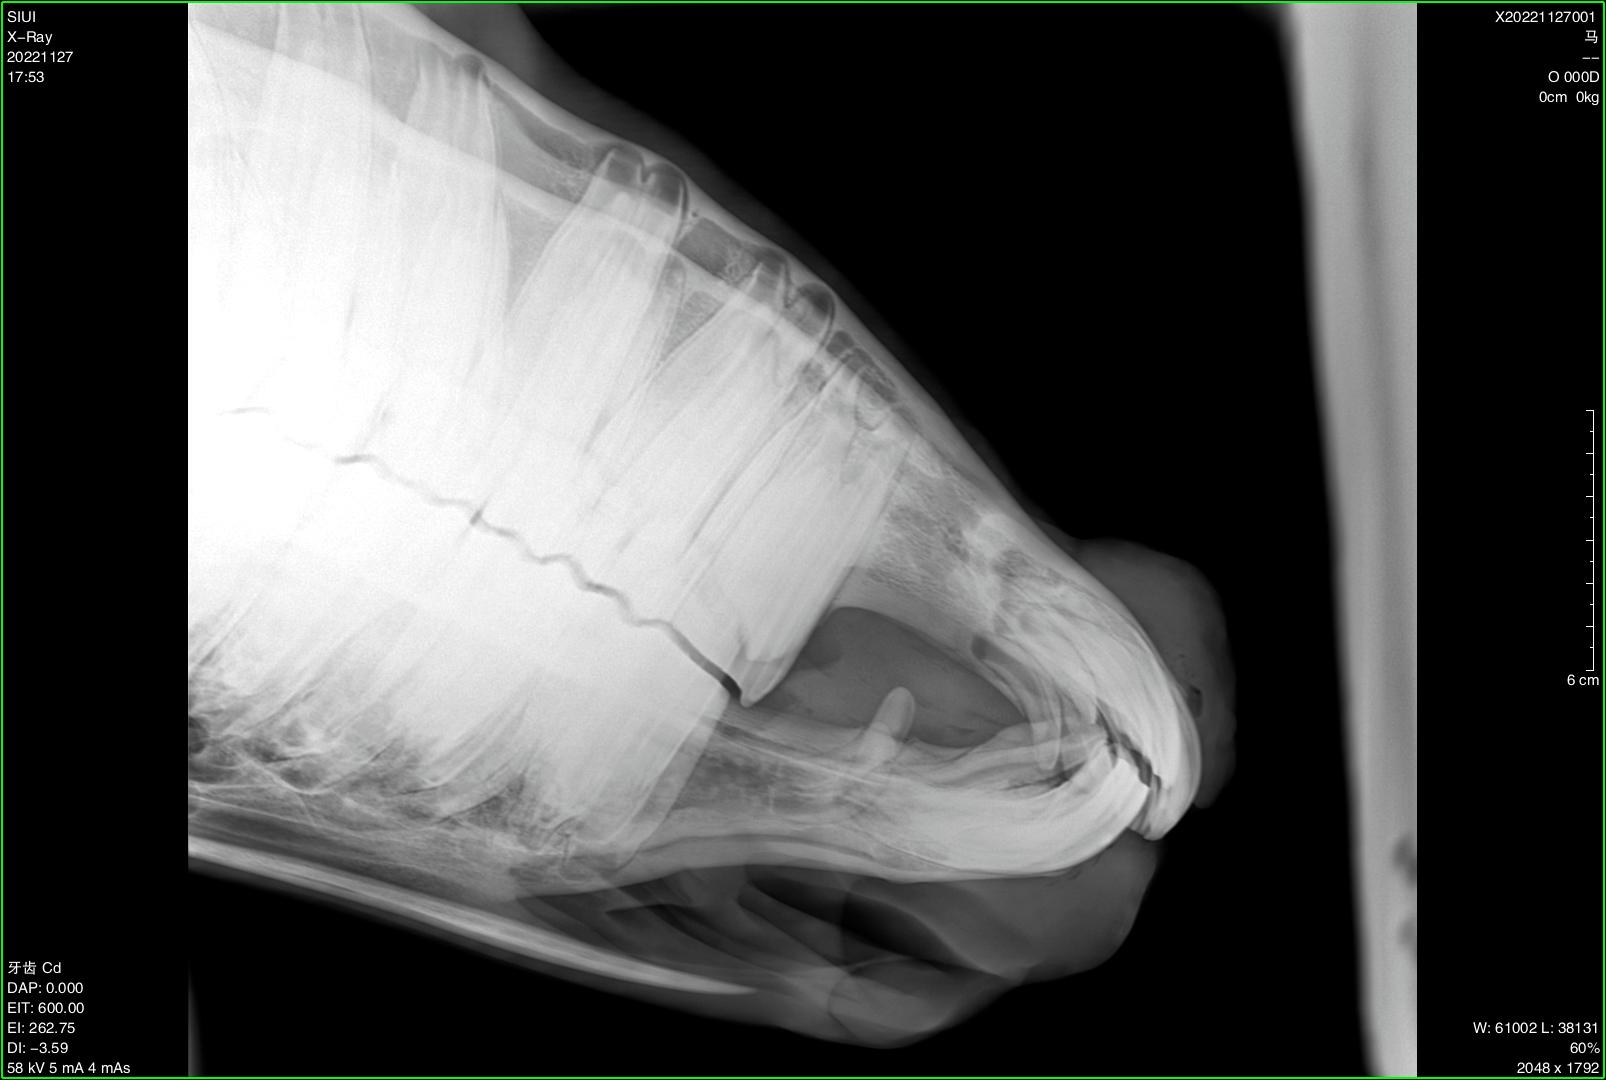

Veterinary Ultra-Portable DR System

SIUI veterinary ultra-portable DR system currently includes 2 models, SR-100 Vet and SR-300 Vet. An ultra-portable DR system consists of an ultra-lightweight X-ray generator, a wireless flat panel detector, and a user-friendly workstation.

The X-ray generators of SR-100 Vet and SR-300 Vet feature different portable designs, thereby accommodating the operational preferences of different veterinarians and adapting to diverse application environments. All-in-one backpacks, suitcases, and various types of stands are available for convenient transportation and application at stables, farms, zoos, etc.

Diverse Application Scenarios:

● Stables